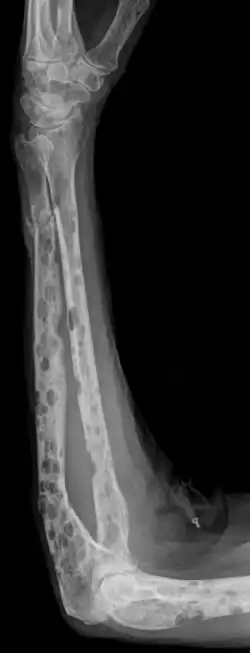

Опухолевая ткань разрастается преимущественно в плоских костях (череп, рёбра, таз) и в позвоночнике, инициируя в них остеолизис[6] и остеопороз. На рентгенограмме очаги поражения имеют вид гладкостенных пробоин. Полости образуются в местах роста миеломных клеток за счёт активации ими остеокластов, осуществляющих лизис и резорбцию костной ткани («пазушное» рассасывание). Помимо костного мозга, опухолевые инфильтраты могут обнаруживаться и в других органах.